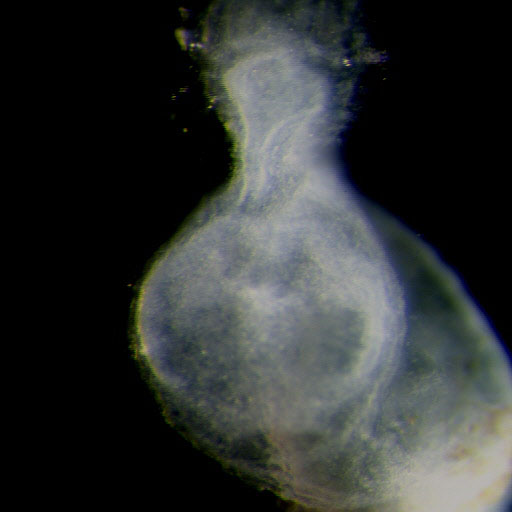

Carnegie Stage 8

Carnegie Stage 8 Definition

Age is approximately 23 postovulatory days

Length is approximately 1 - 1.5mm

External Features Include: the appearance of the primitive pit and the notochordal canal. Somites are not yet visible.